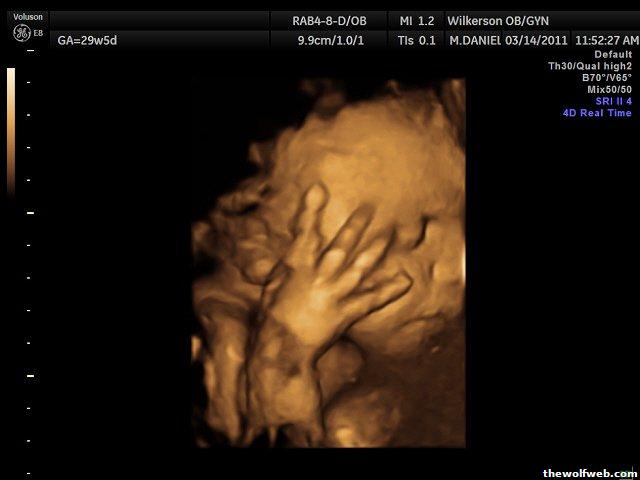

To cheer everyone up, here are pictures from our 3D/4D yesterday.

Estimated Fetal Weight 3lb11oz @ Estimated GA 29wk5dy